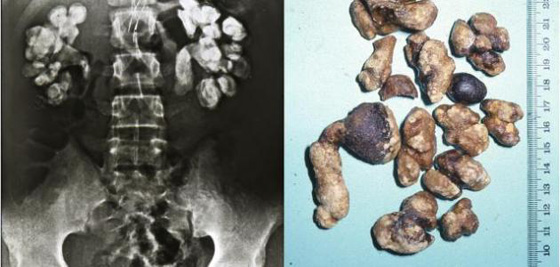

3- تفتيت حصى المثانة

تشير النصوص اليونانية والرومانية والفارسية والهندية القديمة إلى عملية تعرف "بعملية تفتيت الحصاة المثانية"، لاستئصال الحصوة المتكونة في المثانة. خلال هذه العملية، يُطلب من المريض الاستلقاء على ظهره مباعداً بين ساقيه. وفي الأثناء، يتم تمرير شفرة في المثانة من خلال العجان، وهي المنطقة الملساء الواقعة بين كيس الصفن والشرج.

ومما يضفي طابعاً من الإهانة على هذه العملية، قيام الجراحين بإدخال أصابعهم أو أدواتهم الجراحية داخل المستقيم أو مجرى البول للمساعدة على إزالة الحصوة. وبالتالي، يترتب على هذه العملية شعور المريض بآلام مبرحة، علماً أن نسبة الوفاة تحت هذه العملية أو من مضاعفاتها قد تصل إلى 50%. بحلول القرن التاسع عشر، أخذ عدد عمليات تفتيت الحصاة المثانية في التراجع تدريجياً، حيث وقع استبدالها بطرق أكثر إنسانية. كما ساعدت الحميات الغذائية الصحية خلال القرن العشرين على جعل الإصابة بهذا الداء من الحالات الطبية النادرة.